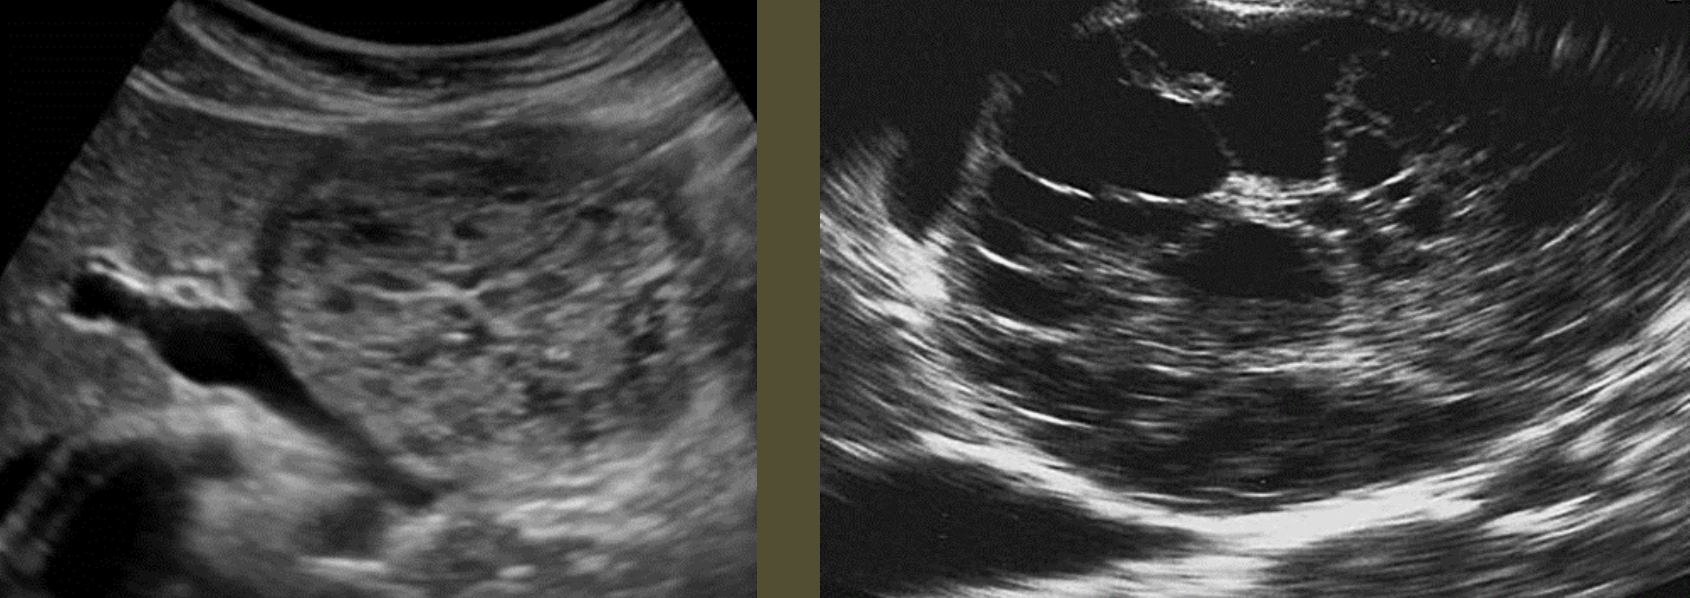

Acute Pancreatitis → sudden inflammation of pancreas from blockage of ducts and increased secretions

2D US: pancreas enlargement, hypoechoic parenchyma from edema, irregular ill-defined borders, peripancreatic free fluid, peripancreatic echogenic inflammatory fat, can have focal areas of inflammation/hypoechoic tissue

color doppler: can have hyperemia

DDX: chronic pancreatitis

Chronic Pancreatitis → recurrent attacks of acute pancreatitis, progressive destruction of pancreatic tissue

2D US: mixed pattern of echogenicity (hyperechoic from fibrosis to hypoechoic from inflammation), calcifications, normal to atrophic size, nodular surface, dilated/calcified pancreatic duct (> 3 mm), solid mass, thrombosis of splenic and portal vein

color doppler:

DDX: acute pancreatitis